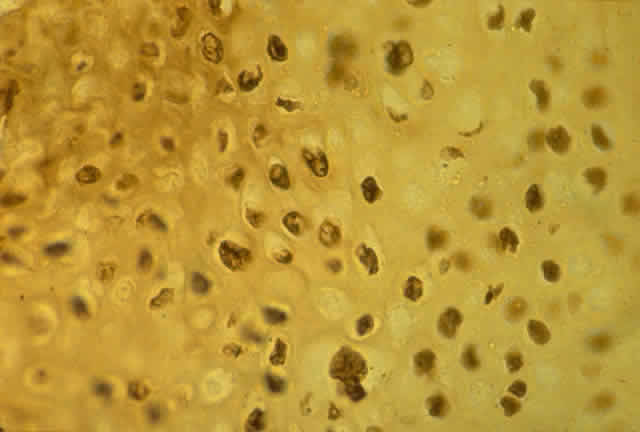

HPV-induced conjunctival squamous papillomas demonstrate papillomatosis, acanthosis, and koilocytosis (Fig. 6). Because they are mucous membrane lesions, those of the conjunctiva and lacrimal sac show no granular cell layer but will show keratinization if they are large or exposed (Fig. 7). In our experience the frequency of koilocytes is variable, even in lesions almost certain to be viral (Fig. 8). Scattered inflammatory cells may be present in the cores or epithelium. Virus can be detected immunohistochemically in the nuclei of the cells (Fig. 9).

Historically, viral involvement was indicated by the presence of koilocytosis. Later, immunohistochemical analysis of HPV-common antigens allowed the first demonstration of viral components in lesional cells (see Fig. 8). Newer, more specific DNA-based techniques allowed typing of viruses. In situ hybridization, which bridged DNA and immunohistochemical techniques, was somewhat more sensitive than either technique alone. The development of PCR amplification allowed detection of a tiny amount of original source DNA and, with proper controls, powerful statements could be made about specific virus involvement. Because DNA is relatively stable compared to many antigens, DNA techniques can be used on archival material or on specimens fixed with aldehydes and embedded in paraffin.